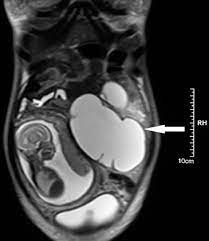

The largest type of ovarian cyst is called a cystadenoma.

Ovarian cysts are either benign or malignant. This isn't the same as cause cancer; Survey reveals widespread ovarian cancer misdiagnosis. In general, ovarian cysts can range from under 0.5 inches (1.27 cm) to more than 12 inches (30.48 cm). Can 19mm ovarian dermoid cyst be mistaken (misdiagnosed) with any another cysts?

Ovarian cancer and cysts have similar symptoms and signs, for example, pain during intercourse, pelvic pain, and urinary problems. After pleading with one doctor to finally listen to her, she got a much more. Mature cystic teratomas, also called dermoid cysts, rarely undergo a malignant transformation, i.e. Yesturday i had keyhole surgery to remove what they thought was just a normal 6cm cyst on my right ovary. Ovarian cancer starts in the cells lining the ovaries. Every year, 7,000 women are diagnosed with ovarian cancer and 4,300 women lose their lives to it. Malignant ovarian cysts are only seen in rare cases, with the benign being the most common of them all. These benign cysts originate from germ or embryonic cells and thus contain different kinds of tissue such as cartilage, bone and skin. However, as women, this is something we need to be talking about. What is dermoid ovarian cyst? The largest type of ovarian cyst is called a cystadenoma. Her surgery was due to multiple painful complex cysts on her uterus. This is one of the main reasons why ovarian cancer is so difficult to detect at an early stage.